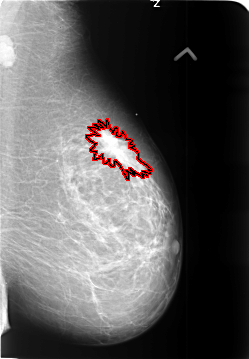

B_3401_1.LEFT_MLO

LEFT_MLO LINES 5744 PIXELS_PER_LINE 3976 BITS_PER_PIXEL 12 RESOLUTION 50 OVERLAY

FILE: B_3401_1.LEFT_MLO.OVERLAY

TOTAL_ABNORMALITIES 1

ABNORMALITY 1

LESION_TYPE MASS SHAPE IRREGULAR-ARCHITECTURAL_DISTORTION MARGINS SPICULATED

ASSESSMENT 5

SUBTLETY 5

PATHOLOGY MALIGNANT

TOTAL_OUTLINES 1

BOUNDARY